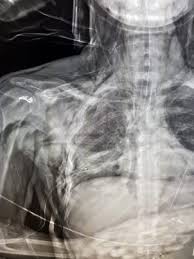

Sonographie Bei Covid 19 Patienten

Sonographie Bei Covid 19 Patienten from cdn0.scrvt.com